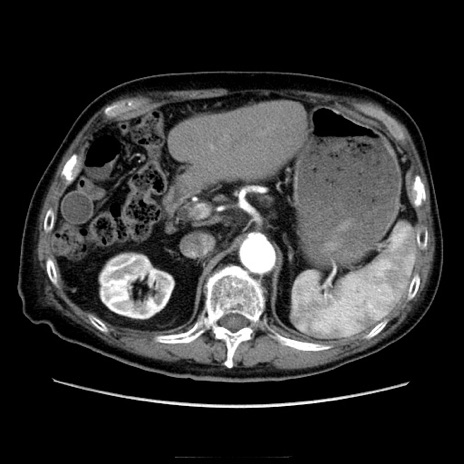

症例21(横断像)

【症例】70歳代男性

【主訴】腹痛

【現病歴】肝硬変・肝細胞癌にてかかりつけの方。約9時間前に食後より腹痛出現。症状が徐々に増悪し、嘔吐出現したため来院。

【既往歴】肝硬変、肝細胞癌(RFA、TACE後)

【身体所見】意識清明、表情苦悶様、BT 36℃、BP 129/78mmHg、P 88bpm、SpO2 97%(RA)、右上腹部から心窩部にかけて圧痛あり、反跳痛なし、筋性防御あり。

【データ】WBC 5800、CRP 0.16